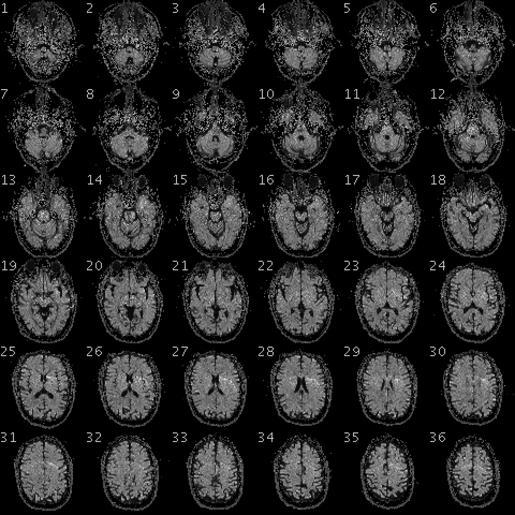

MAKE A MEME View Large Image 100325 RS88UH 11 qc.gif en fMRI of the brain/head of a PGP participant with the following data Demographic Information Date of Birth 1954-08-28 58 years old Gender Male Weight 246lbs 112kg Height 6ft 5in 195cm Blood Type O+ Race White https ...

Keywords: 100325 RS88UH 11 qc.gif en fMRI of the brain/head of a PGP participant with the following data Demographic Information Date of Birth 1954-08-28 58 years old Gender Male Weight 246lbs 112kg Height 6ft 5in 195cm Blood Type O+ Race White https //my personalgenomes org/profile/hu43860C Personal Genome Project https //my personalgenomes org/profile/hu43860C PGP Scientists 2010-04-29 cc-zero To the extent possible under law PersonalGenomes org has waived all copyright and related or neighboring rights to Personal Genome Project Participant Genetic and Trait Dataset This work is published from United States Magnetic resonance imaging Personal Genome Project